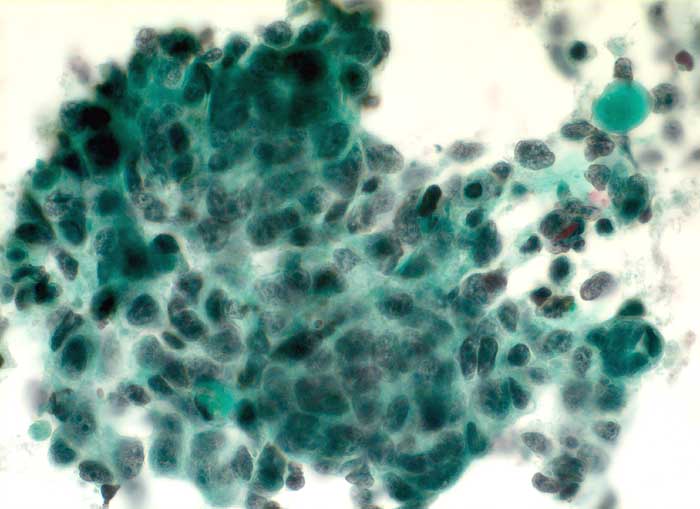

Die meisten Hirnmetastasen stammen von Karzinomen, wobei Mamma- und Bronchuskarzinome am häufigsten sind. Im Unterschied zu allen primären Hirntumoren bilden Karzinommetastasen Verbände. Am schwierigsten ist die Differentialdiagnose von Glioblastoma multiforme und grosszelligem Karzinom. In beiden Fällen sind Tumornekrosen typisch. Auch bei einem Karzinom kann der Hintergrund neurofibrilläre Matrix aus dem umgebenden Hirngewebe enthalten. Kleinzellige Karzinome müssen von Lymphomen und Medulloblastomen abgegrenzt werden.

Unten finden Sie Beispiele von Metastasen eines Plattenepithelkarzinoms, eines Adenokarzinoms und eines kleinzelligen Karzinoms.